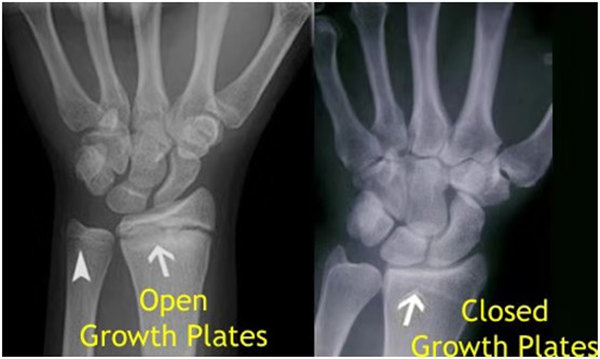

其實想要了解孩子的生長發育情況或者說孩子未來身高的趨勢,測骨齡是個好辦法。臨床上通常拍攝兒童的左手正位X光片 , 采用《中華-05》骨齡標準對手腕骨發育程度進行骨齡評價。

我們都知道,人體的高矮是由骨骼的生長發育決定的,特別是下肢長骨。長骨呈長管狀,在長骨的兩端有一種專管骨骼生長的骺軟骨,它與干骺端之間有一盤狀軟骨結構稱為骺板(線),在幼兒的X光片上表現為一條較寬的透光帶。 (見下圖)

未成年時隨著年齡的增加骺軟骨端不斷骨化,骨骼就不斷增長。當骨骺線完全閉合時骨骼就停止生長,個子也就不再增長了。一般骨骺端完全閉合的年齡是18~20歲左右。